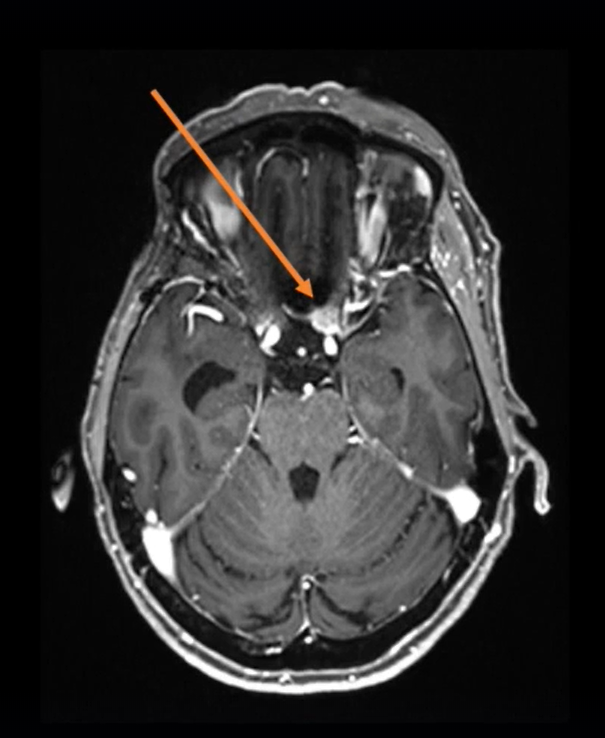

▼下右额下入路肿瘤全切术

图2:手术入路,右额下入路(入路方向大致如图)

为什么Froelich教授会选择经额下入路?额下入路是Cushing提出的探查鞍区肿瘤的开颅方法,一直沿用至今,适用于肿瘤累及视神经者。另外对鞍结节脑膜瘤、颅咽管瘤、视神经胶质瘤,都可以采用这种开颅方法。额叶下入路较易显露肿瘤,不影响视神经。在视交叉沟(蝶缘)的前肢钻孔可使视神经管的内侧面充分显露。额下入路为对侧交叉沟和视神经提供较好手术轨迹。当对视神经管内侧进行钻孔时,在直接观察视神经下内侧的情况下,可以顺利地切除伸入视神经管的肿瘤。

图3:额下开颅术